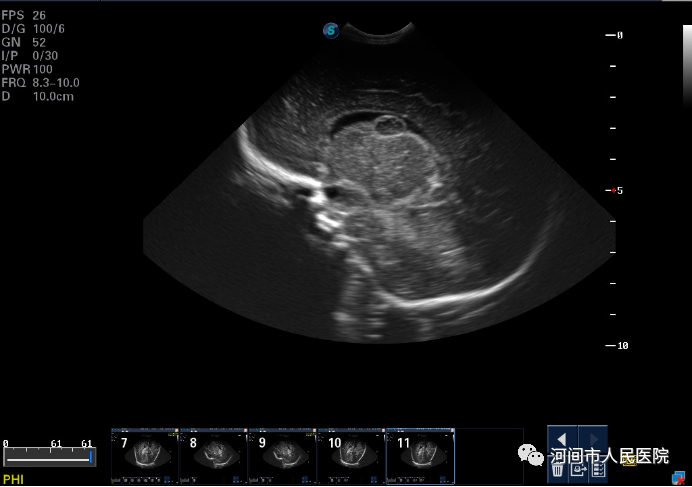

▲新生兒(er) 室管膜下囊腫